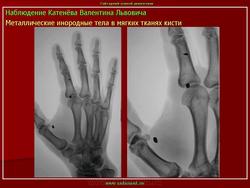

Инородное тело - зуб в пищеводе.

Приложения:

inorodnoe_telo_obstrukcii._-zub_v_pishchevode.jpgzub.jpg